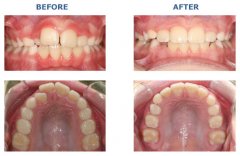

牙齿不齐怎么办?

随着现代口腔医疗技术的发展,牙齿不整齐 的问题也可以得到矫正,让牙齿重...【详细】